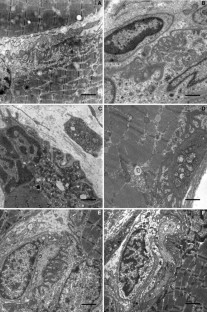

Spinal muscular atrophy with respiratory distress type 1 (SMARD1) is genetically and clinically distinct from classic spinal muscular atrophy (SMA1). It results from mutations in the gene encoding immunoglobulin μ-binding protein 2 (IGHMBP2) on chromosome 11q13. Patients develop distally pronounced muscular weakness and early involvement of the diaphragm, resulting in respiratory failure. Sensory and autonomic nerves are also affected at later stages of the disease. We investigated peripheral nerves, skeletal muscles and neuromuscular junctions (NMJ) ultrastructurally in five unrelated patients and three siblings with genetically confirmed SMARD1. In mixed motor and sensory nerves we detected Wallerian degeneration and axonal atrophy similar to the ultrastructural findings described in SMA1. Isolated axonal atrophy was evident in purely sensory nerves. All investigated NMJ of patients with SMARD1 were dysmorphic and lacked a terminal axon. Moreover, we also observed characteristics of neuropathies, such as abnormalities in myelination, that have not been described in spinal muscular atrophies so far. Based on these findings we conclude that impairment of IGHMBP2 function leads to axonal degeneration, abnormal myelin formation, and motor end-plate degeneration.

Fig. 2 A